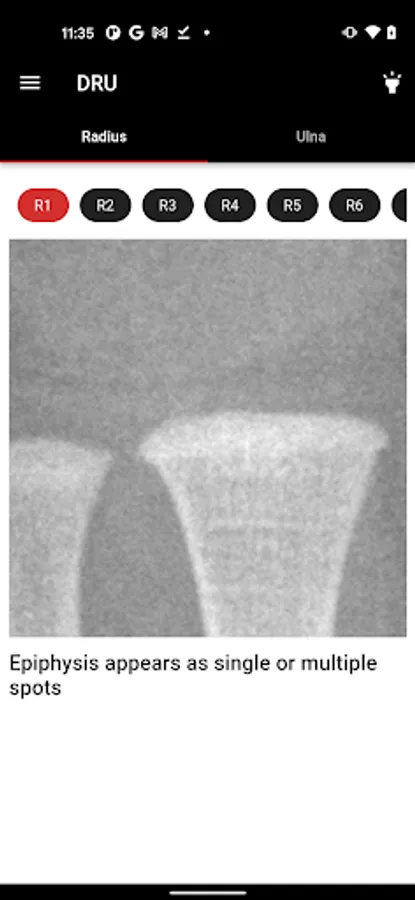

2. Distal radius and ulna features on x-rays for grading